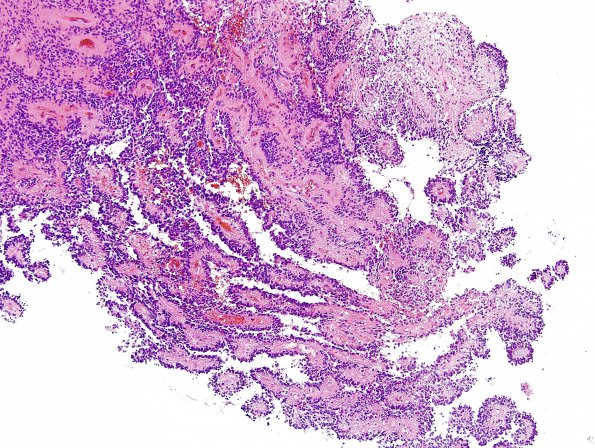

Washington University Experience | NEOPLASMS (GLIAL) | Ependymoma - Microscopic | 12B1 Ependymoma, anaplastic (Case 12) H&E 10

12B1-5 This is a hypercellular glial neoplasm with a nodular and trabecular architecture that forms numerous perivascular rosettes and true 'ependymal' rosettes that have central lumens and terminal bars. The neoplastic cells have predominantly ovoid nuclei with mild contour irregularities, stippled chromatin, and inconspicuous nucleoli. They have indistinct cell-cell borders and fibrillary cytoplasm oriented in a tangential fashion with respect to adjacent rosettes. Portions of the specimen are markedly hypercellular and show easily identified and numerous mitoses [i.e. 3 mitoses observed in a single high power (40x objective) field]. Although many portions of the specimen show a single layer of cells surrounding rosettes, there are also numerous areas where nuclei show variable degrees of overlap, crowding, and multi-layering. Portions of the specimen show necrosis and the presence of a mixed inflammatory infiltrate.